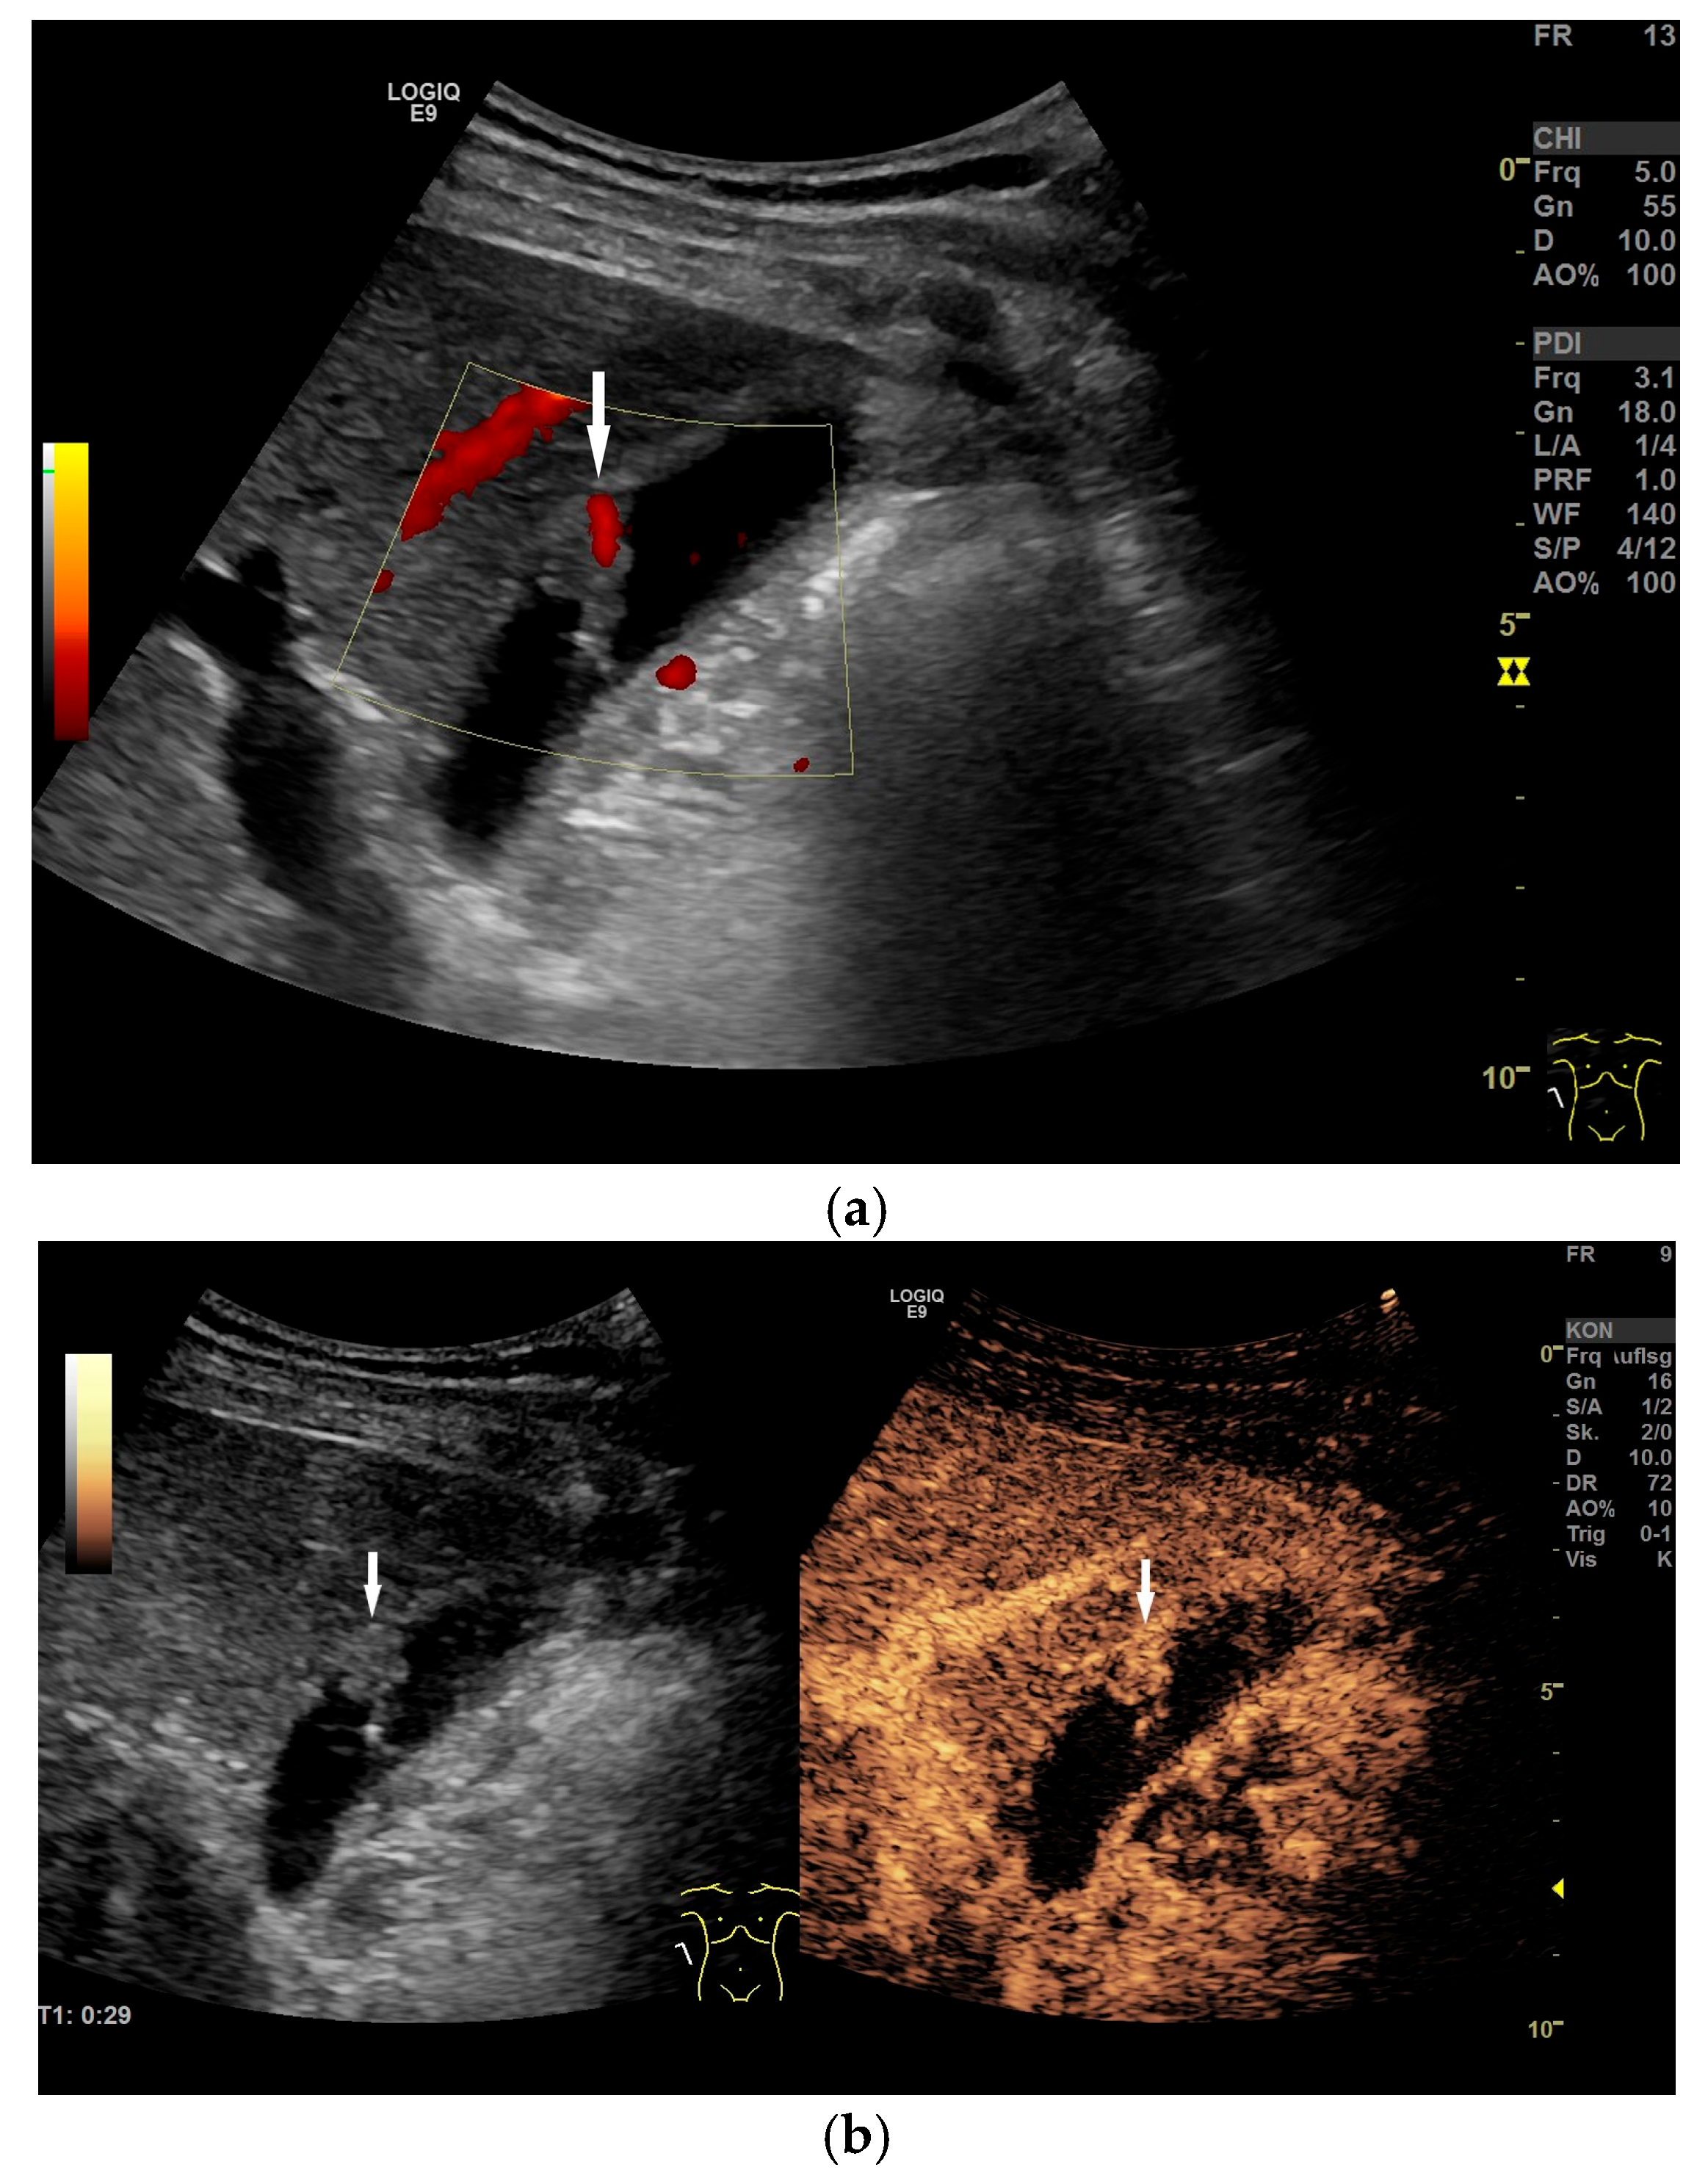

4.1. Diffuse Gallbladder Wall Thickening

- Vriesman, A.C.v.B.; Engelbrecht, M.R.; Smithuis, R.H.M.; Puylaert, J.B.C.M. Diffuse gallbladder wall thickening: Differential diagnosis. Am. J. Roentgenol. 2007, 188, 495–501. [Google Scholar] [CrossRef]

- Gupta, P.; Marodia, Y.; Bansal, A.; Kalra, N.; Kumar-M, P.; Sharma, V.; Dutta, U.; Sandhu, M.S. Imaging-based algorithmic approach to gallbladder wall thickening. World J. Gastroenterol. 2020, 26, 6163–6181. [Google Scholar] [CrossRef]

- Verma, A.; Kumar, I.; Yadav, Y.; Kumar, S.; Puneet; Shukla, R.C.; Verma, A. Utility of contrast-enhanced ultrasound in differentiation between benign mural lesions and adenocarcinoma of gallbladder. J. Med. Ultrasound 2020, 28, 143–150. [Google Scholar] [CrossRef]